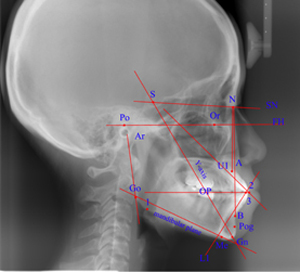

6﹒同時擁有2D與3D資料管理系統,增加影像分析的準確性。

7﹒可匯入Dicom影像檔,並可存成其他看圖格式,方便影像資料

.......操作分析。